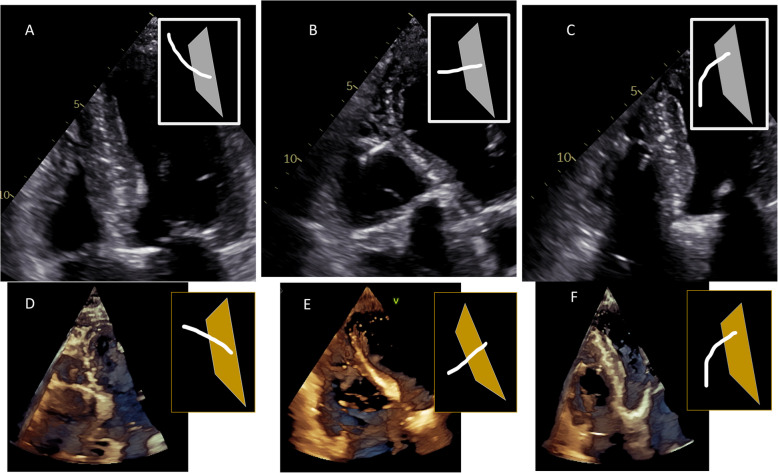

Conduction system pacing (CSP), encompassing His-bundle pacing (HBP) and left bundle branch area pacing (LBBAP), revolutionizes cardiac pacing, allowing a more physiological left ventricular activation than conventional right ventricular (RV) pacing through electrode placed in RV apex, interventricular septum or right ventricular outflow tract. Echocardiography plays a pivotal role in patient assessment, primarily by measuring left ventricular ejection fraction (LVEF) to determine the pacing strategy in alignment with current guidelines. Clinical data, simulations and ongoing trials on CSP explore CSP viability across various LVEF conditions. CSP is supposed to defer pacing-induced cardiomyopathy (PiCM) associated with conventional right ventricular pacing (RVP). This paper aims to review the current literature regarding the use of echocardiography in CSP. Images from our experience in the echocardiographic lab were used throughout this document to show our proposals of imaging in CSP. Echocardiography may help to determine lead localization within the interventricular septum (IVS), customizing pacing to individual anatomy and electromechanical indices (like atro-ventricular delay) and evaluates often-overlooked valvular function, a potential PiCM contributor. Three-dimensional (3-D) echocardiography widens the knowledge of lead localization and valvular dysfunction, as well as dyssynchrony assessment. Dyssynchrony, crucial both to resynchronization per se and physiological stimulation is quantified via echocardiography, especially using speckle-tracking imaging. Baseline LVEF and follow-up observation of CSP effects: early in Global Longitudinal Strain (GLS), afterwards in LV volumes and LVEF may improve the future proper qualification of patients. Limited left atrial (LA) and right atrial (RA) strain assessments hold potential in the CSP qualification and response assessment context. Echocardiography complements other imaging modalities for comprehensive patient evaluation. Echocardiography is integral in the CSP clinical use, from patient selection (by showing subtle changes in myocardial function) to post-procedure follow-up (tricuspid regurgitation, LV and RV function, leads and synchrony assessment). GLS, assessed by speckle tracking imaging and profound 2D and 3D (lead placement, septum morphology and global heart function under CSP) analyses show promise in CSP outcome assessment, though standardization is needed.